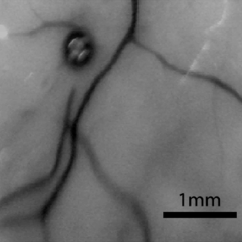

Govindahari V., Dornier R., Ferdowsi S., Moser C., Mantel I., Behar-Cohen F., Kowalczuk L., High-Resolution Adaptive Optics-Trans-scleral Flood Illumination (AO-TFI) Imaging of Retinal Pigment Epithelium (RPE) in Central Serous Chorioretinopathy (CSCR), Scientific Reports, 14.1 (2024):13689. doi: 10.1038/s41598-024-64524-4. |

Kowalczuk L., Dornier R., Kunzi M., Iskandar A., Misutkova Z., Gryczka A., Navarro A., Jeunet F., Mantel I., Behar-Cohen F., Laforest T., Moser C., in vivo Retinal Pigment Epithelium Imaging using Transscleral OPtical Imaging in healthy eyes, Ophthalmology Science, 100234 (2022). |

dos Santos F., Laforest T., Künzi M., Kowalczuk L., Behar-Cohen F., and Moser C., Fully automated detection, segmentation, and analysis of in vivo RPE single cells, Eye, June 2020. |

Laforest T., Künzi M., Kowalczuk L., Carpentras D., Behar-Cohen F. and Moser C. , Transscleral optical phase imaging of the human retina, Nature Photonics, March 2020. |